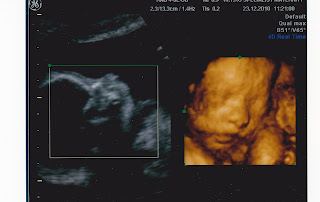

~> Hajat untuk menimang cahayamata kedua tercapai pada Julai 2010, insyallah awal April 2011 akan menyambut ahli keluarga baru sebagai penambah seri lagi dalam keluarga kami